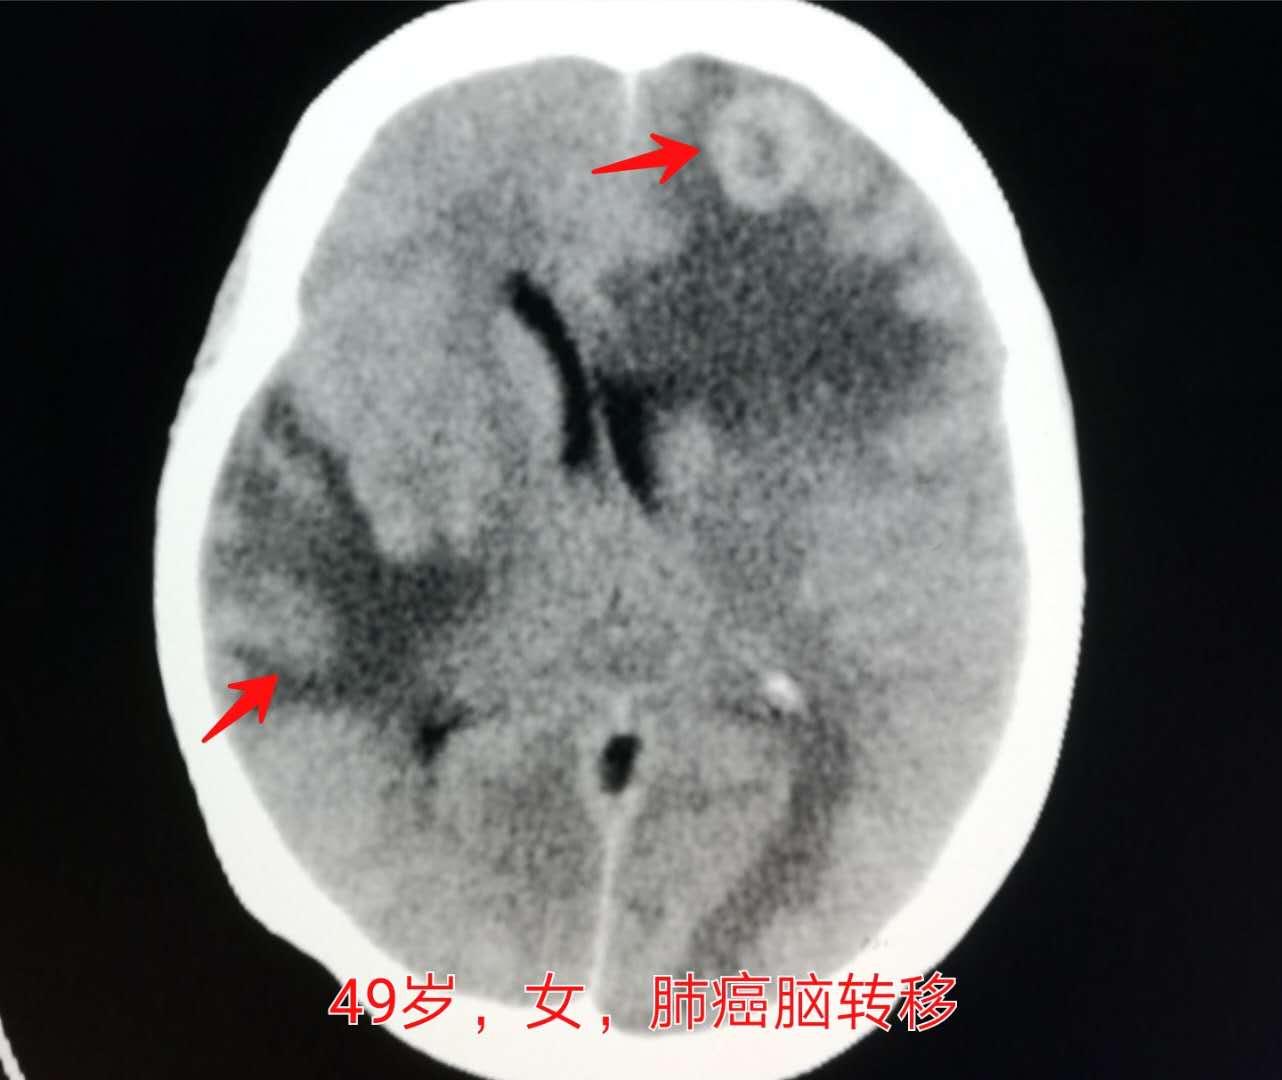

下图这位49岁的女性,说是最近记性不好,老忘事儿,以为是到更年期了?提前脑萎缩了?

神经内科医生说,做个脑CT看看吧:

结果发现了脑多发转移瘤。

脑转移瘤的CT表现:

转移瘤在颅脑CT上,可呈等密度、低密度和高密度,其密度决定于肿瘤细胞成分、血供以及瘤组织有无坏死、囊变和出血、钙化等。

肺、乳腺、肾及结肠癌的转移多为低密度;淋巴瘤及黑色素瘤转移则常表现为高密度或等密度。转移瘤出血常见于肾癌、乳腺癌、黑色素瘤和绒癌,肿瘤有新鲜出血会呈高密度。转移瘤钙化常见于骨、软骨肉瘤转移。

转移瘤的一个显著特征是周围常见明显低密度水肿,影像上呈指状分布。

CT增强扫描会显示更多细节特征,还有助于小病灶的检出。绝大多数转移瘤血供丰富,且肿瘤血管没有血-脑屏障,强化明显。实质性肿瘤多呈明显均匀强化,而坏死囊变者多呈环形强化,可有结节状突起(壁结节)。